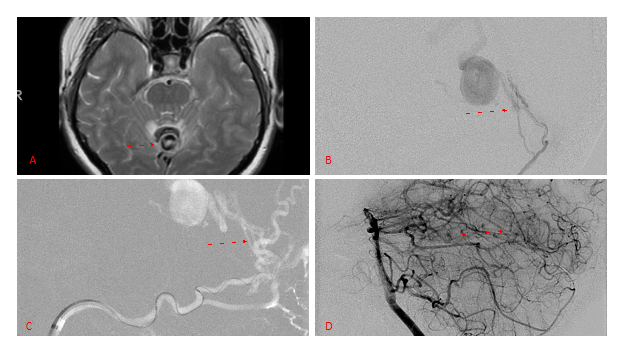

A 55-year-old woman presented with acute onset of severe headache, and possible witnessed seizure. Imaging confirmed intraventricular hemorrhage primarily focused within the fourth ventricle with diffuse subarachnoid hemorrhage within the posterior fossa and along the tentorium as observed on non-contrast CT and MRI of the Brain (Figure 1).

Figure 1. A and B) Non-Contrast CT Axial and Coronal demonstrate large, ruptured Varix/Aneurysm along the Incisura of the posterior fossa which appears to have mixed hemorrhagic components and enhancement on MRI T2 and post contrast imaging (C and D).

No severe neurologic deficits were observed initially. Her cerebral angiogram revealed a high flow Dural arterial venous fistulous malformation of the tentorium supplied by the bilateral external carotid and left vertebral arteries into a large venous varix within the fourth ventricle at the site of the hemorrhage. Deep venous drainage is observed into the Galenic and Straight Sinus of the posterior fossa (Figure 2).

Figure 2. [A] Ruptured Varix/Aneurysm of the Deep Venous Posterior Fossa drainage and AV shunting (arrows) [B] Posterior Meningeal Artery Fistula [C] Right Middle Meningeal Artery Fistula [D] Post embolization Left Vertebral Angiogram demonstrates resolution of the high flow and pressure A-V Shunting following successful embolization with liquid embolic (NBCA).